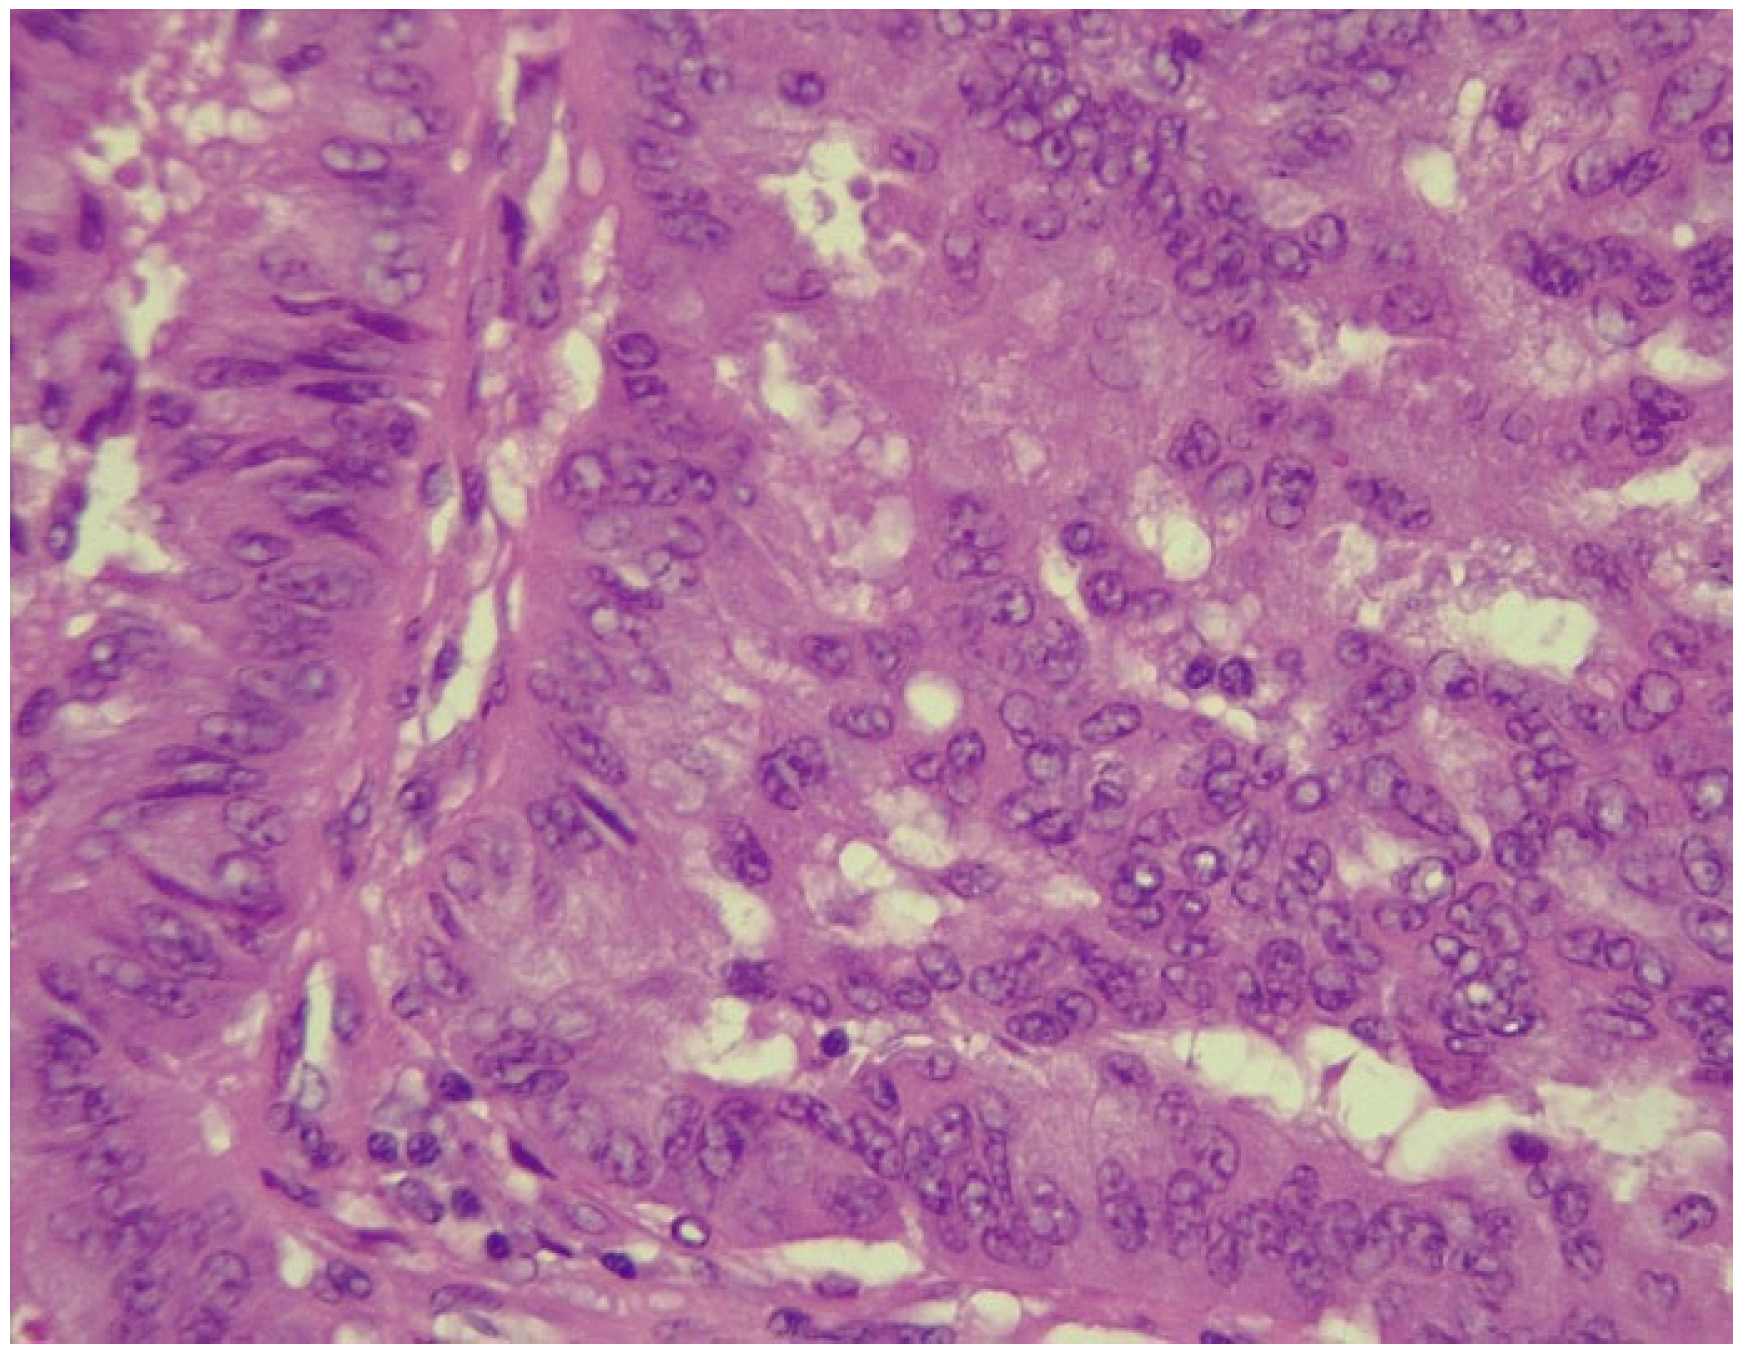

2. Case Report